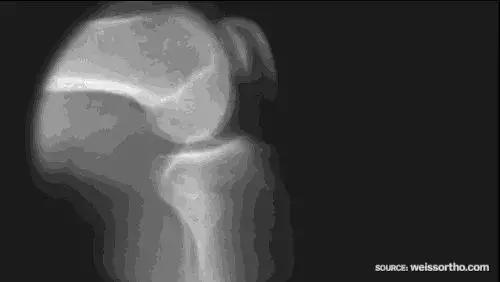

人体的关节有“使用寿命”,如果年龄达到了关节的使用寿命,关节处的软骨会变薄、软化、失去弹性,甚至碎裂、剥脱,软骨下的骨质增生并形成骨赘(即所谓“骨刺”),最终导致关节疼痛、关节僵硬和活动受限,这便是骨关节炎。

关节炎是最常见的慢性病之一,被定义为头号致残性疾病,类风湿性关节炎被称为“不死的癌症”。我国约有1.2亿人患有骨关节炎,几乎每10人中就有一个。关节炎发病呈年轻化趋势,膝关节衰老从30岁开始。